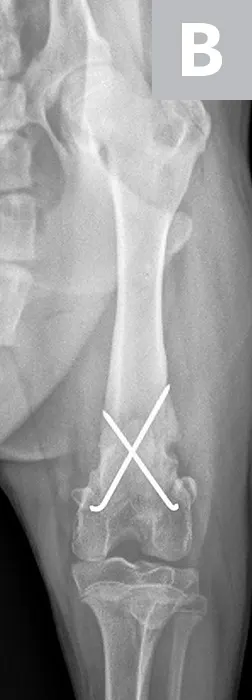

Hydromorphone (0.05 mg/kg IV) was administered for analgesia, and lateral and ventrodorsal thoracic radiographs were obtained to evaluate for thoracic trauma. Radiographic findings were within normal limits; however, lateral and craniocaudal radiographs of the right pelvic limb (Figure 1) revealed a Salter-Harris type II fracture of the distal femur with caudal and medial displacement.

Figure 1

Lateral (A) and craniocaudal (B) radiographs of this patient’s femur. A Salter-Harris type II fracture with caudal and medial displacement is present in the distal femur. The metaphyseal component (A; arrow) and the epiphyseal component (arrowhead) can be noted.